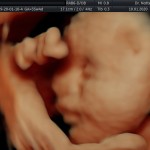

- Crecimiento fetal.